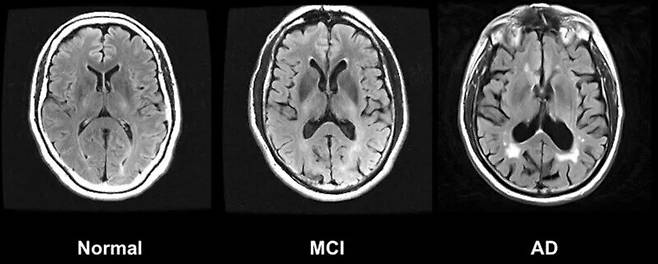

요약 : 신경퇴행성 질환은 전 세계의 약 6900만명이 앓고 있으며 매년 증가할 것으로 예상되어 전세계적인 보건 문제로 여겨져왔다. 국제 공공-민간 연구협력기관인 ‘글로벌 신경퇴행성 단백질체학 컨소시엄’(GNPC)은 2억5000만건 이상의 측정값이 포함된 신경퇴행성 질환 관련 단백질 데이터세트를 완성하고 네이처 메디신에 논문을 발표하였으며, 연구진은 이와 같은 데이터가 조기 진단 및 예후 개선에 도움을 줄 것으로 기대하고 있다. 빌 게이츠는 알츠하이머병 진단이 더 이상 사형 선고가 아닌 날이 그 어느 때보다 가까워졌다며 긍정적인 태도를 보였다. 오스트레일리아 시드니대의 케이틀린 피니 교수가 중심이 된 연구진, 미국 스탠퍼드대의 토니 와이스-코레이 교수가 중심이 된 연구진 등은 단백질의 변화가 인지 기능과 어떤 상관관계가 있는지 밝혀내며 새로운 치료법을 밝혀내고 있는 가운데, 빌 게이츠는 최근 미국 국립보건원(NIH)과 다른 정부 기관의 예산 삭감 등으로 데이터 세트 핵심 구성 요소인 최첨단 생화학 지문 데이터 공급이 중단될 위기에 처해 있으며 치매에 대한 새로운 흐름을 만들어낸 시점에 서 있는 지금 연구를 중단해서는 안된다고 강조하고 있다.